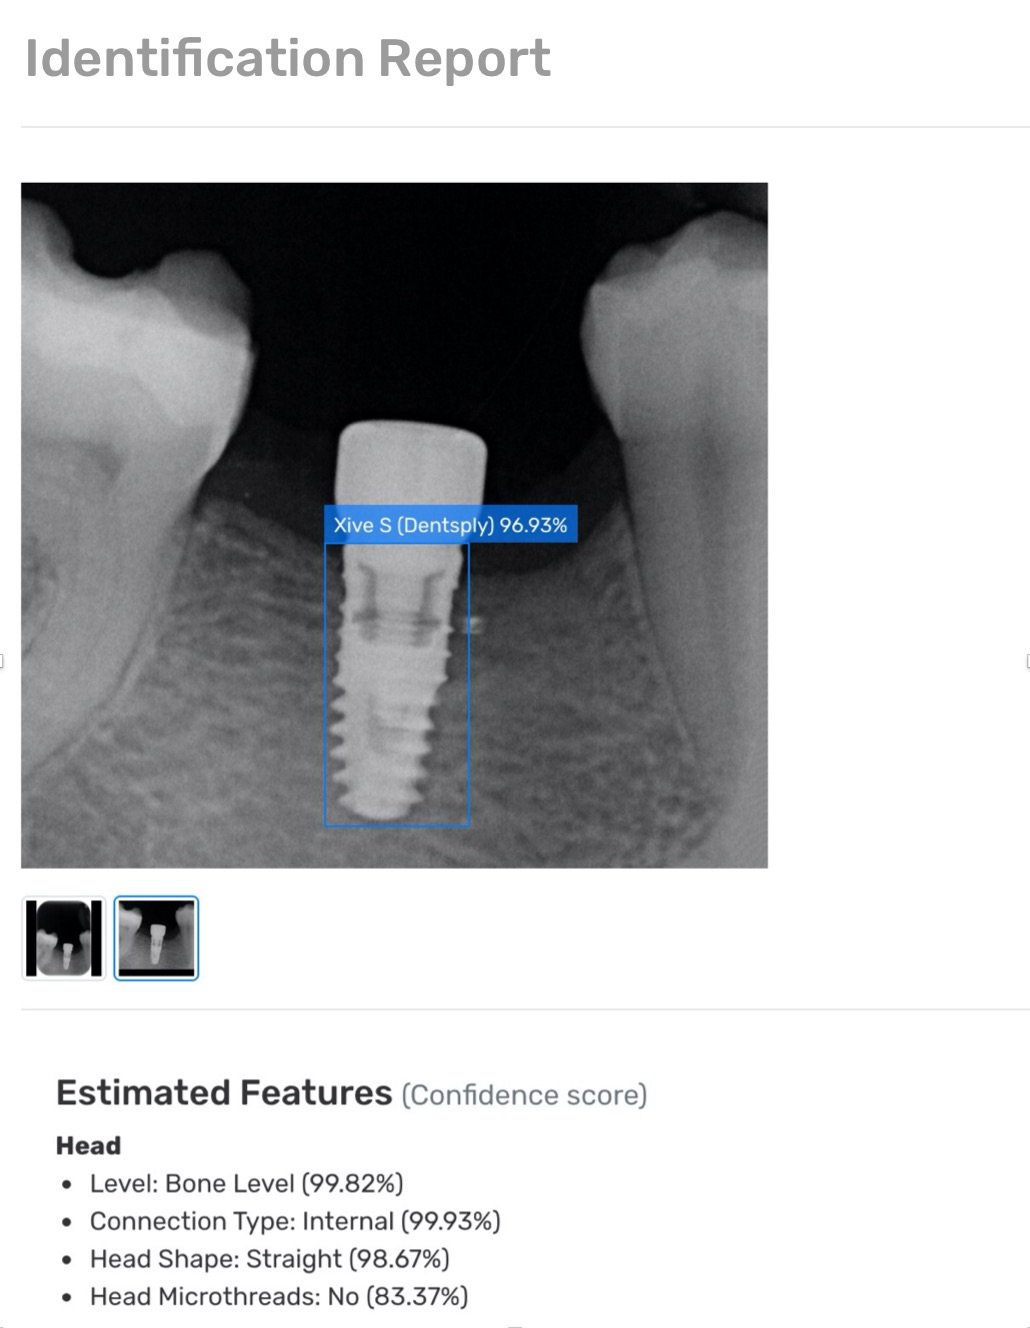

Holen Sie sich Ihren Identifikationsbericht

KI-basierte

Eigener Deep-Learning-Algorithmus

Von Experten entworfen

Vorhersagen über technische Merkmale, Abmessungen, ähnlichste Implantate etc.

Haben Sie als Zahnarzt oder Zahnchirurg vielleicht schon einmal Schwierigkeiten gehabt, ein Implantat zu identifizieren? Vielleicht hat der Patient seinen Implantatpass verloren, die Rückverfolgbarkeit des Implantats ist nicht mehr gegeben, und Sie fragen sich, um welches Implantat es sich handelt? Bei Tausenden von Zahnimplantaten auf der Welt ist es unmöglich, ein unbekanntes Zahnimplantat zu erkennen, um einfache prothetische Versorgungen durchzuführen. Je nach klinischer Situation ist es jedoch manchmal notwendig, Behandlungen an einem Implantat vorzunehmen, insbesondere bei lockerer Prothese, Kronenwechsel, Knochenverlust oder Periimplantitis. Aus diesem Grund haben wir die Spotimplant-Anwendung zur Implantatidentifizierung entwickelt. Auf der Grundlage einer einfachen Röntgenaufnahme, vorzugsweise einer periapikalen Röntgenaufnahme, kann unser Service die Marke und das Modell des Implantats ermitteln. Das System basiert auf Deep-Learning-Algorithmen und stützt sich auf die umfangreichste Implantatdatenbank der Welt. Spotimplant liefert technische Details wie Anschlüsse und Schraubendreher und leitet Sie bei der Suche nach kompatiblen prothetischen Komponenten, Teilen, Attachments und anderen Produkten an. Wann immer Sie sich die Frage stellen: "Welches Implantat ist das?" (what implant is that.), sind wir zur Stelle, um Ihnen zu helfen. So können Sie sich auf den wichtigsten Teil Ihrer Arbeit konzentrieren: die qualitativ hochwertige Versorgung Ihrer Patienten, um ihnen ein schönes Lächeln und schöne Zähne zu schenken. Auf diese Weise erhöht Spotimplant die Lebensdauer und Langlebigkeit von Implantaten.

Spotimplant ist die erste auf künstlicher Intelligenz basierende Implantaterkennungssoftware, eine E-Health-Anwendung in der Implantologie/Zahnmedizin, die ein konkretes Problem des Berufsstandes aufgreift, das bisher noch nicht gelöst wurde. Heute wird das System von Zahnärzten auf der ganzen Welt genutzt.